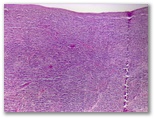

r2A ¿lINFOMA?

Diagnostico